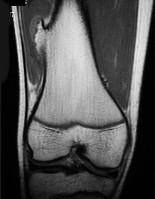

男,13岁,运动后膝痛,请结合影像图像,选择最可能的诊断()A.正常影像B.动脉瘤样骨囊肿C.骨软骨瘤D.成骨细胞瘤E.骨样骨瘤

问题 男,13岁,运动后膝痛,请结合影像图像,选择最可能的诊断()

选项 A.正常影像 B.动脉瘤样骨囊肿 C.骨软骨瘤 D.成骨细胞瘤 E.骨样骨瘤

答案 C